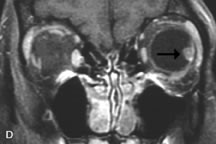

Tl relaxation time is the time required for the energized nuclei to give up the excess energy that was acquired from the RF pulse (high-energy state) and re-establish equilibrium (low-energy state) with the main magnetic field. The excess energy is released by these excited nuclei to the surrounding molecular environment, or lattice, and results in T1 relaxation, also called spin-lattice relaxation time. In different biologic tissues, hydrogen has a Tl ranging from a few hundred milliseconds to a couple of seconds. This range exists because local tissue factors affect the ability of specific protons to give up energy to the surrounding tissues. For example, hydrogen atoms attached to the carbon atoms of fat molecules relax much more rapidly than those attached to the oxygen atoms of water molecules. Viscosity, concentration, temperature, and molecular environment of the hydrogen atoms in the tissues also affect the T1 relaxation time. On a T1-weighted orbital image, fat, which has a very short T1 relaxation time, yields a high-intensity signal; the rectus muscles, which have an intermediate T1, yield an intermediate-intensity signal; and the vitreous, which has a long T1, yields a low-intensity signal (Fig. 8).5,8,16

Application of a 90° RF pulse brings the excited nuclei into phase so that the net vector of their magnetic moments is directed perpendicular to the static magnetic field. Shortly thereafter, the magnetic moments of the nuclei spread out and point in different directions, leading to a loss of phase coherence and a resultant decay in signal intensity amplitude. The T2, or spin-spin relaxation time, is the rate of decrease in the signal of these excited nuclei as a result of the interaction and transfer of energy to unexcited adjacent nuclei. T2 ranges from a few milliseconds to a few hundred milliseconds and, for a given tissue, is always less than the Tl relaxation time. T2-weighted orbital images are easily recognized by a high-intensity signal from the vitreous (Fig. 9).5,8,16

CONTRAST AGENTS